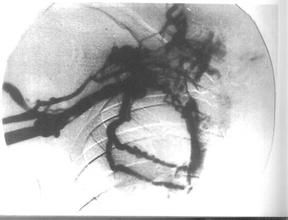

靜脈造影下肢靜脈造影屬於四肢靜脈造影最常見的一種,在臨床中運用較多。造影主要是為了確診有無深靜脈血栓形成,深靜脈和淺靜脈交通支瓣脈是否健全,以及探討小腿慢性潰瘍的病因等。本文收集我院外科1996年5月~2003年5月疑為下肢靜脈曲張需手術而做術前檢查、主要檢查深靜脈功能情況且造影比較成功、臨床資料比較完整者60例,總結分析如下。 一般資料本組共60例,男46例,女14例,年齡39~69歲。臨床均表現為下肢靜脈曲張10年以上,28例發生於雙下肢,19例發生在右側,13例發生在左側;38例出現慢性潰瘍等。 方法所有造影均在AXGPSM801000MAX光透視下觀察並點片。患者仰臥在床面,下肢稍外鏇,頭高足低約15°。由於本組病例都以檢查深靜脈功能為臨床主要目的,故在踝部縛一橡皮止血帶,鬆緊以僅能阻斷下肢淺靜脈回流為宜。從足背淺靜脈中注入泛影葡胺20ml,電視透視下在15s內注射完畢,在造影劑注入3/4時開始從踝至髖部攝片,必要時改變體位後局部加攝點片。 在本組病例中,造影表現為下肢深靜脈正常,交通靜脈被逆向充盈,不少造影劑通過交通靜脈進入曲張的皮下淺靜脈者42例,造影表現為一般深靜脈無明顯瓣膜陰影,管壁尚光整或輕度不規則者13例,局部深靜脈欠規則和擴大者5例,兩者均可見並伴有交通靜脈和淺靜脈逆向充盈。其中曲張的淺靜脈血栓形成2例。造影表現為下肢深靜脈、交通支正常,擴張的淺靜脈無一例被造影劑逆向充盈。 正常下肢靜脈行走方向數目較不固定,但主要的靜脈還是可以辨認的,一般由3組互相交通的靜脈所組成:淺組、深組和交通靜脈。顯影的靜脈有光滑平行的管壁,從遠端到近端管壁逐漸自下而上,由淺入深正常回流的瓣膜,在靜脈壁上每隔一定距離可見瓣膜對稱圓形凸出。位於大隱靜脈上端的瓣膜甚堅強,能阻止股靜脈的血液倒流入大隱靜脈[1]。下肢血管造影術有靜脈造影和動脈造影兩種方法,但靜脈造影簡單,容易掌握,較適用於基層醫院,使用得當一般能滿足診斷要求。本組由於臨床造影前已基本診斷了下肢靜脈曲張,主要目的是觀察深靜脈及交通靜脈的通暢情況,故本文重點討論有關這方面的內容。 下肢靜脈曲張是常見的周圍血管疾病之一,主要發生在淺的大隱靜脈,其次在小隱靜脈。深靜脈的瓣膜較淺靜脈多且受肌肉的保護,一般多不發生曲張。當靜脈曲張時,瓣膜產生關閉不全,更加重了靜脈的擴張、彎曲、延長。如同時有交通靜脈瓣膜損壞,則血液可自深靜脈返流至淺靜脈,淺靜脈負擔增重使曲張嚴重。後期周圍組織缺氧發生營養不良可出現血腫、色素沉著和潰瘍,本組有38例。曲張可分為3類:(1)單純性淺靜脈瓣膜功能不全症狀較輕,故本組無一例。(2)交通靜脈瓣膜功能不全,本組有42例。(3)交通靜脈和深靜脈的功能不全,本組有18例,其中深靜脈功能不全較嚴重者6例。 下肢靜脈造影不僅可以了解靜脈曲張阻塞的部位、程度,而且可以判斷側支循環建立的情況。本組造影目的主要是為了配合臨床下肢靜脈曲張手術的術前檢查,為臨床手術方法方案的制定提供可靠的依據,以減少此病復發率。本組60例造影中基本上解決了臨床的要求,故有明顯的針對性及專一性。